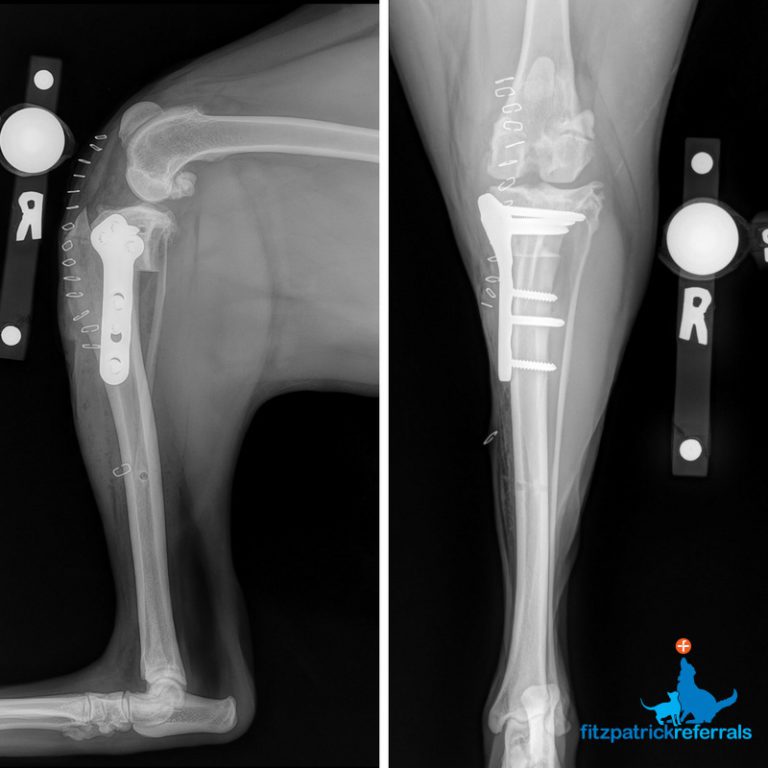

From www.fitzpatrickreferrals.co.uk

Lilly and Tara's TPLO surgery Fitzpatrick Referrals Tplo Surgery Gone Wrong a tibial plateau leveling osteotomy (tplo) is one of several potential surgical procedures to repair a torn acl in. an understanding of the potential complications following tplo surgery can help guide therapy and enable improved client counseling. the signs of tplo failure and complications in dogs is something you may be wondering about if your dog just. Tplo Surgery Gone Wrong.